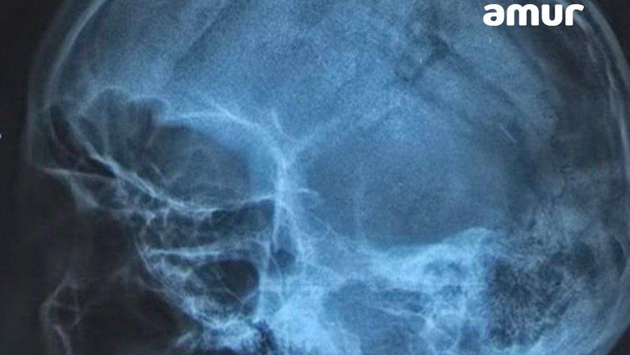

Некоторое время назад в больницу Владивостока доставили мужчину с острова Попова. У 50-летнего гражданина была разбита голова. Снимок показал, что череп проломлен в нескольких местах. Также выяснилось, что у пациента началось кровоизлияние в мозг. Сам он впал в шоковое состояние.

Врачи провели долгую и сложную операцию, в ходе которой смогли собрать череп буквально по кусочкам. Некоторые фрагменты пришлось убрать вовсе. Состояние пациента стабильное.